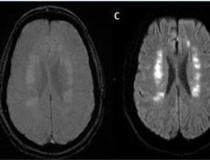

Stroke seen in a 41-year-old male patient with COVID-19 infection. Image courtesy of RSNA

Acute anterior cerebral artery/middle cerebral artery watershed infarction seen in a 47-year-old male patient who presented with COVID-19 pneumonia. Image courtesy of RSNA